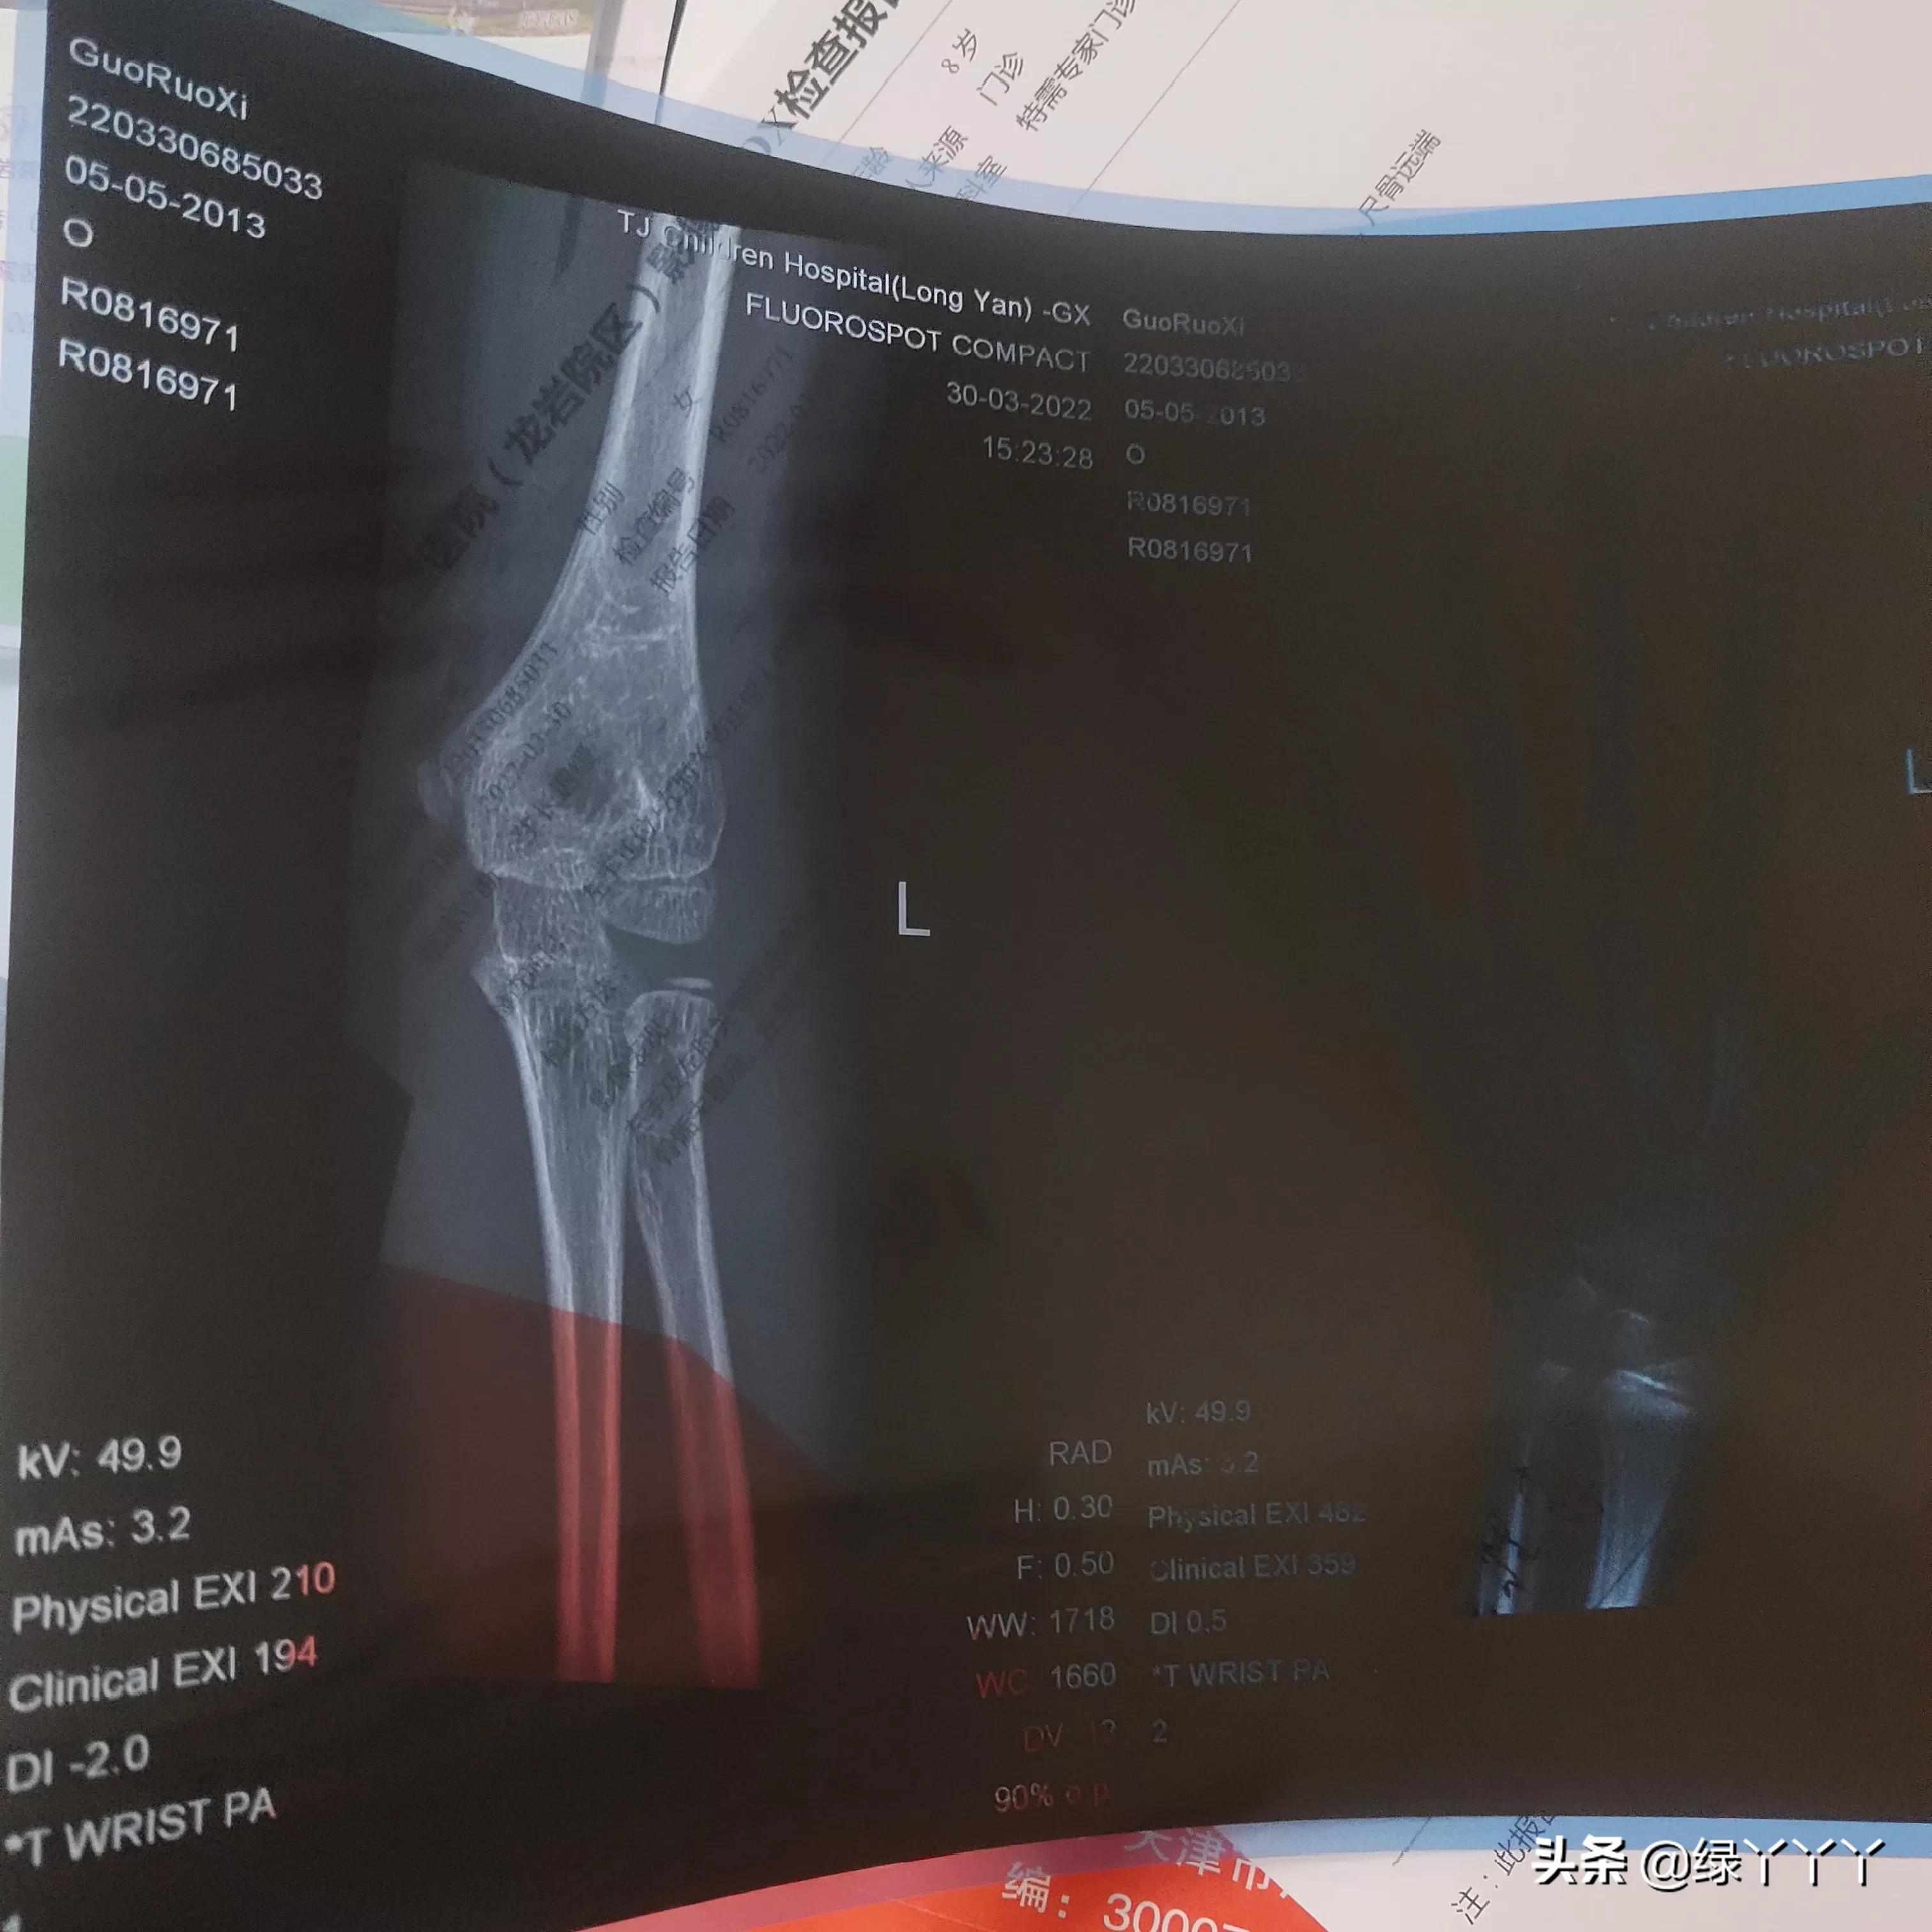

身高124,差一个月9周,体重近46斤,骨龄偏小2岁,医生首先建议 三点 :